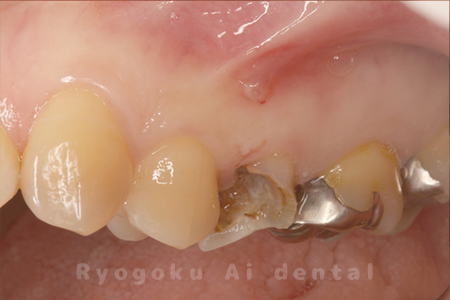

Case03

- 原因

- 重度縁下カリエス

- 治療期間

- 約2ヶ月(最終補綴装着まで含む)

- 治療内容

- クラウンレングスニング+歯周外科

- 治療費用

- 44,000円(最終補綴を除く)

他院で抜歯を宣告された患者様です。虫歯が歯茎の中まで及んでいたため、歯周外科・クラウンレングスニングを行い、保存を行いました。

<リスク・副作用>

手術後は痛み、腫れ、痺れ、青あざなどの副作用が生じます。痛みは痛み止めを処方しますが、腫れ、青あざは1週間程度生じる場合があります。また、部位によっては神経の走行が複雑で、痺れが残り、長期的にお薬を処方する場合があります。